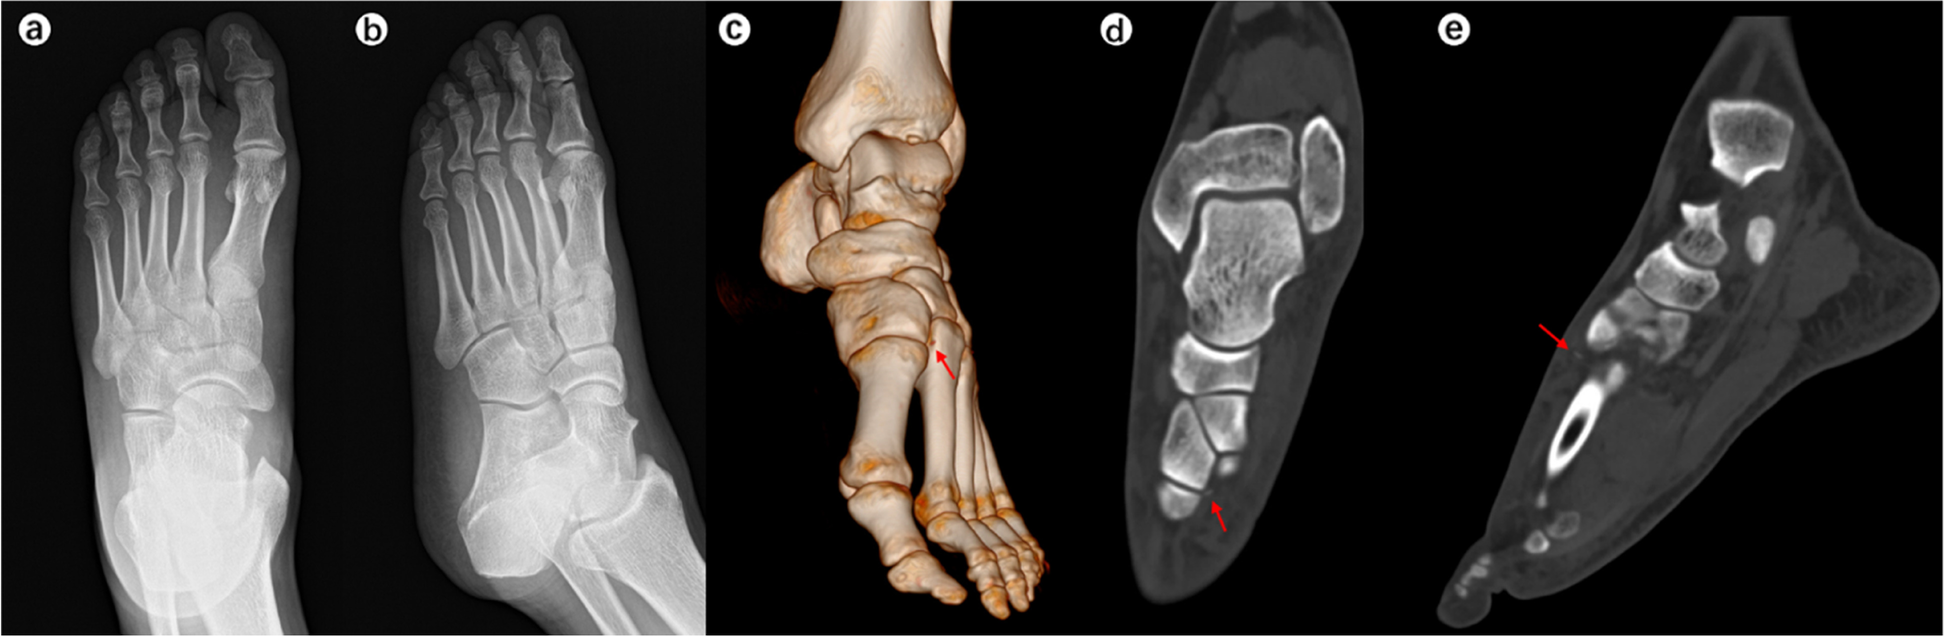

When the surgeons were asked to re-evaluate their initial treatment strategies after assessing the CT images (Table 5), the mean alteration rate was 21.9% (observer A, 28.3%; observer B, 15.6%). This represented a significant difference in alteration rates between the two observers (p < 0.001). Typical case images are shown in the figures (Figs. 1, 2, 3 and 4).

A 42-year-old man had a traffic collision and hurt his right foot. Chiodo-Myerson’s classification: three-column injury; Displacement classification: displaced injury. Both two observers made the correct diagnosis for two times, and didn’t change the initial treatment option (surgery) after evaluating CT image. a-b The conventional radiographs showed obvious tarsometatarsal joint dislocation (red arrows). It was easily diagnosed. c-f CT unraveled more details: intra-articular fractures of the base of the second and third metatarsal bone as well as extensive dorsal-lateral dislocation of the tarsometatarsal joint. The red arrow indicates the fracture fragments